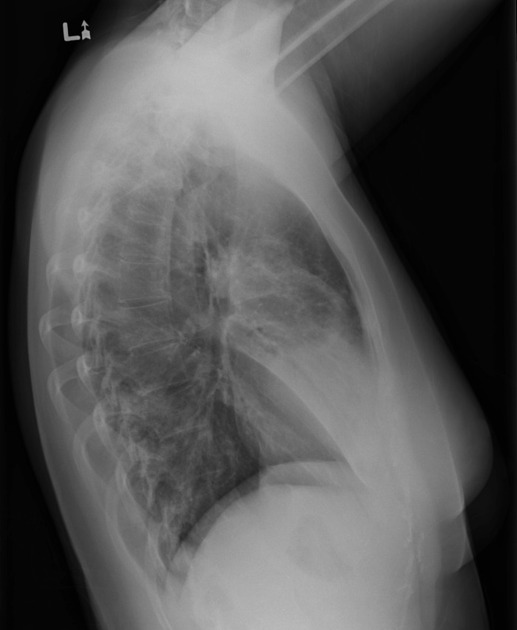

Young female patient with fever, cough and dyspnea.

Diagnosis? Image

Consolidation of the anterior segment of the RUL and the middle lobe of the right lung.

Moderate volume loss of the middle lobe. Image

Demonstration of Felson's silhouette sign.

On the PA view, the anterior segment consolidation is seen superior to the minor fissure of the right lung.